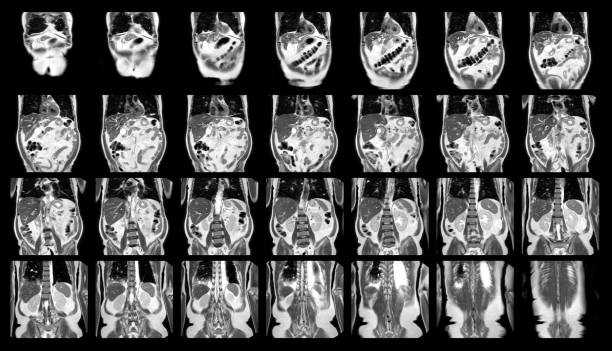

아래 영상의 경우 담도암 이란 어떤 증상과 특징이 있는지 자세하게 설명해주는 영상입니다.

전문의사가 직접 설명하기 때문에 담도암 이란 어떤 암인지 정확하게 이해하실 수 있습니다.